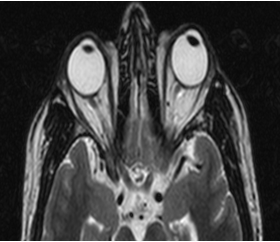

Automated visual field perimetry (OS) showed paracentral scotoma. VEP showed prolonged P100 latency in left eye. MRI orbit showed tortuosity, altered signal intensity with prominence in cerebrospinal fluid sleeve of left optic nerve ([Figure 2]).